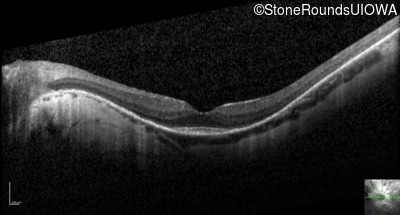

Optical Coherence Tomography - Right - 20/25

Exemplar / OCT Stack

OCT Stack